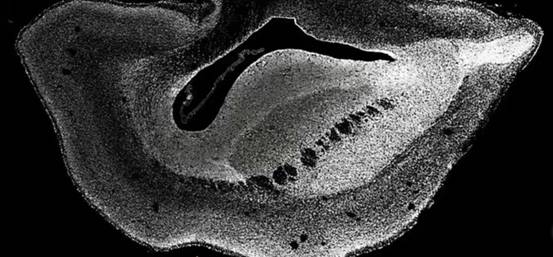

实验结果令人惊讶,在植入了DNA片段“ARHGAP11B”之后,培育出的7个狨猴胚胎,大脑竟然开始了飞速发育。

而且从发育的情况来看,开始出现了很多和人类一样的大闹特征——脑容积不断变大,同时表皮层出现了褶皱结构,显然,这意味着拥有DNA片段“ARHGAP11B”之后,实验的狨猴都开始变得更为聪明。